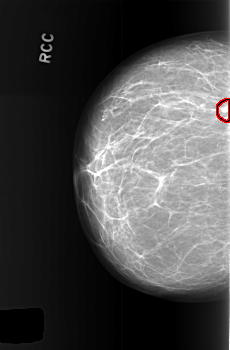

C_0446_1.RIGHT_CC

RIGHT_CC LINES 5600 PIXELS_PER_LINE 3672 BITS_PER_PIXEL 12 RESOLUTION 50 OVERLAY

FILE: C_0446_1.RIGHT_CC.OVERLAY

TOTAL_ABNORMALITIES 1

ABNORMALITY 1

LESION_TYPE MASS SHAPE LOBULATED MARGINS CIRCUMSCRIBED

ASSESSMENT 3

SUBTLETY 5

PATHOLOGY BENIGN_WITHOUT_CALLBACK

TOTAL_OUTLINES 1

BOUNDARY